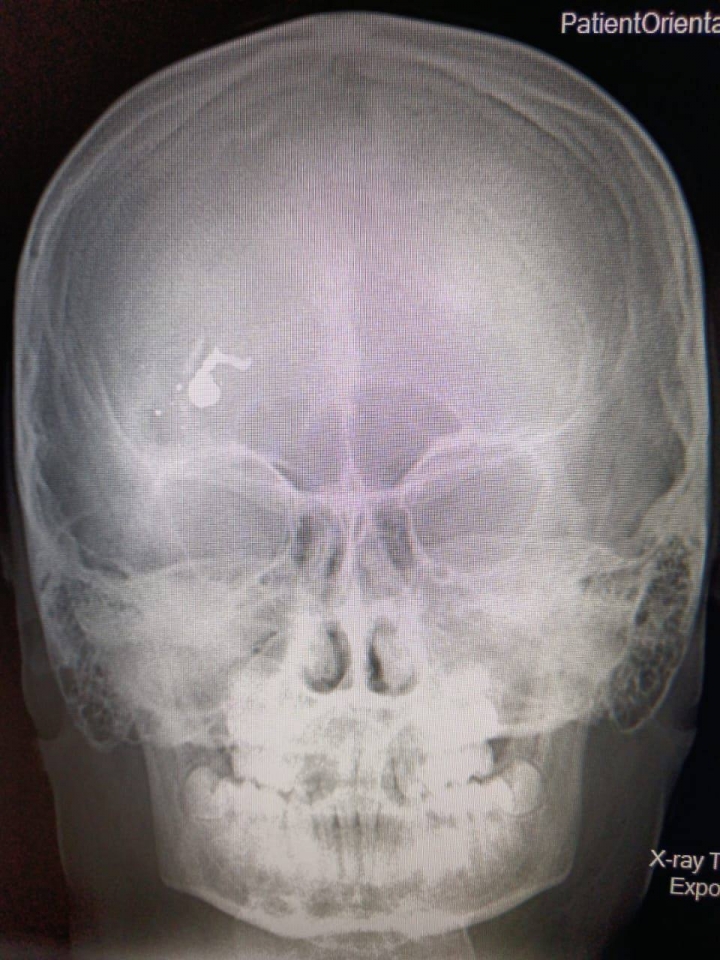

В Саратовской области произошел инцидент, который привлек внимание общественности. Ребенок получил травмы при пока невыясненных обстоятельствах, что вызывает множество вопросов и опасений. Местные жители отмечают, что данная ситуация не только трагична, но и требует тщательного расследования.

По предварительным данным, инцидент произошел в одном из населенных пунктов региона. Власти и правоохранительные органы уже начали проверку, чтобы выяснить все обстоятельства произошедшего. Важно установить, каким образом ребенок оказался в опасной ситуации, и было ли это связано с халатностью взрослых.